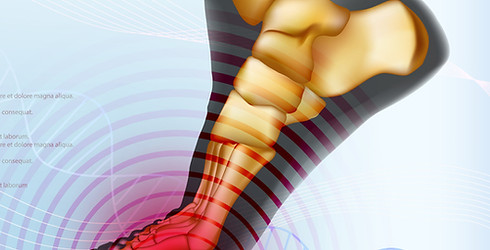

強剛母趾

母趾の付け根にある関節(中足趾節関節)に起こる変形性の関節症です。関節の痛みやこわばりを引き起こし、時間の経過とともに足の指を曲げることが難しくなっていきます。

外反母趾と痛みを感じる部位が類似していますが、外反母趾ほど見た目の変形は生じません。強剛母趾は関節が硬直して動かすことができず、反らす動作が困難になる疾患です。